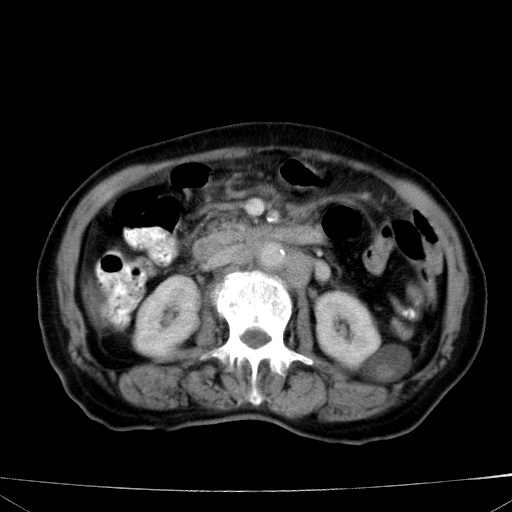

网站人气太旺!昨天的帖子就沉到海底,只好再发贴!ct18338:女 78岁,肝胆病变,已增强,再会诊!原帖链接:http://www.radida.com/bbs/forum.php?mod=viewthread&tid=50032

1)考虑胆囊癌侵犯肝脏并肝门区、腹膜后及右侧膈角后淋巴结转移。2)肝左叶近肝顶部囊肿。3)肝左叶肝内胆管结石。4)左肾近下极囊肿。